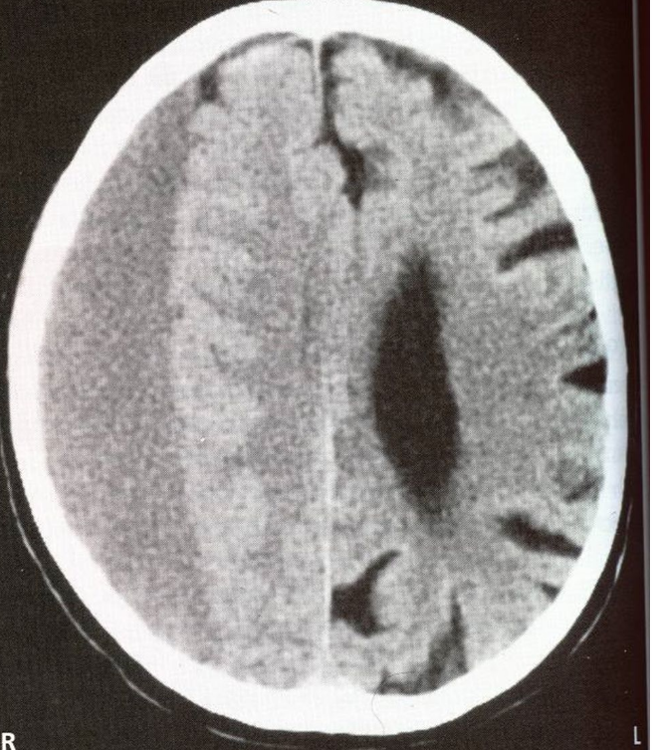

neck

brow, eye, face, lips, jaw, tongue, pharynx, larynx